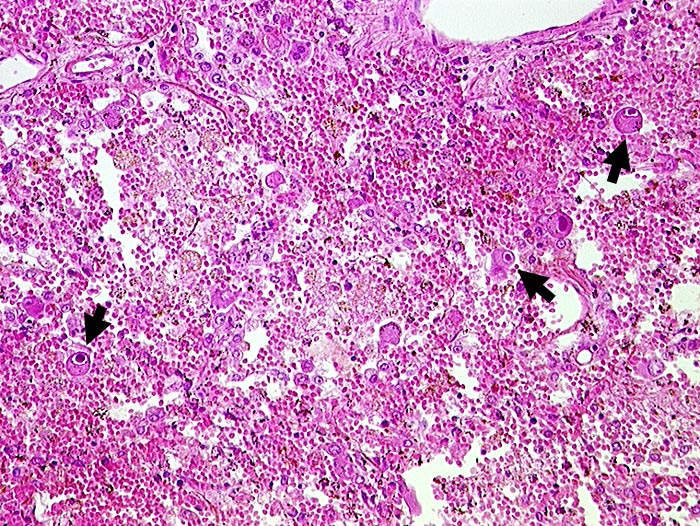

CMV (Zytomegalie) Pneumonie

► Virale Kerneinschlüsse mit Halo in Pneumozyten (sogenannte Eulenaugenzellen). Intraalveoläre Hämorrhagie.

HIV positiv seit 5 Jahren. Nachweis von zytomegalen Zellen im Hirn, in der Lunge, im Gastrointestinaltrakt, den Nieren und der Nebenniere. Zusätzlich bakterielle Pneumonie.